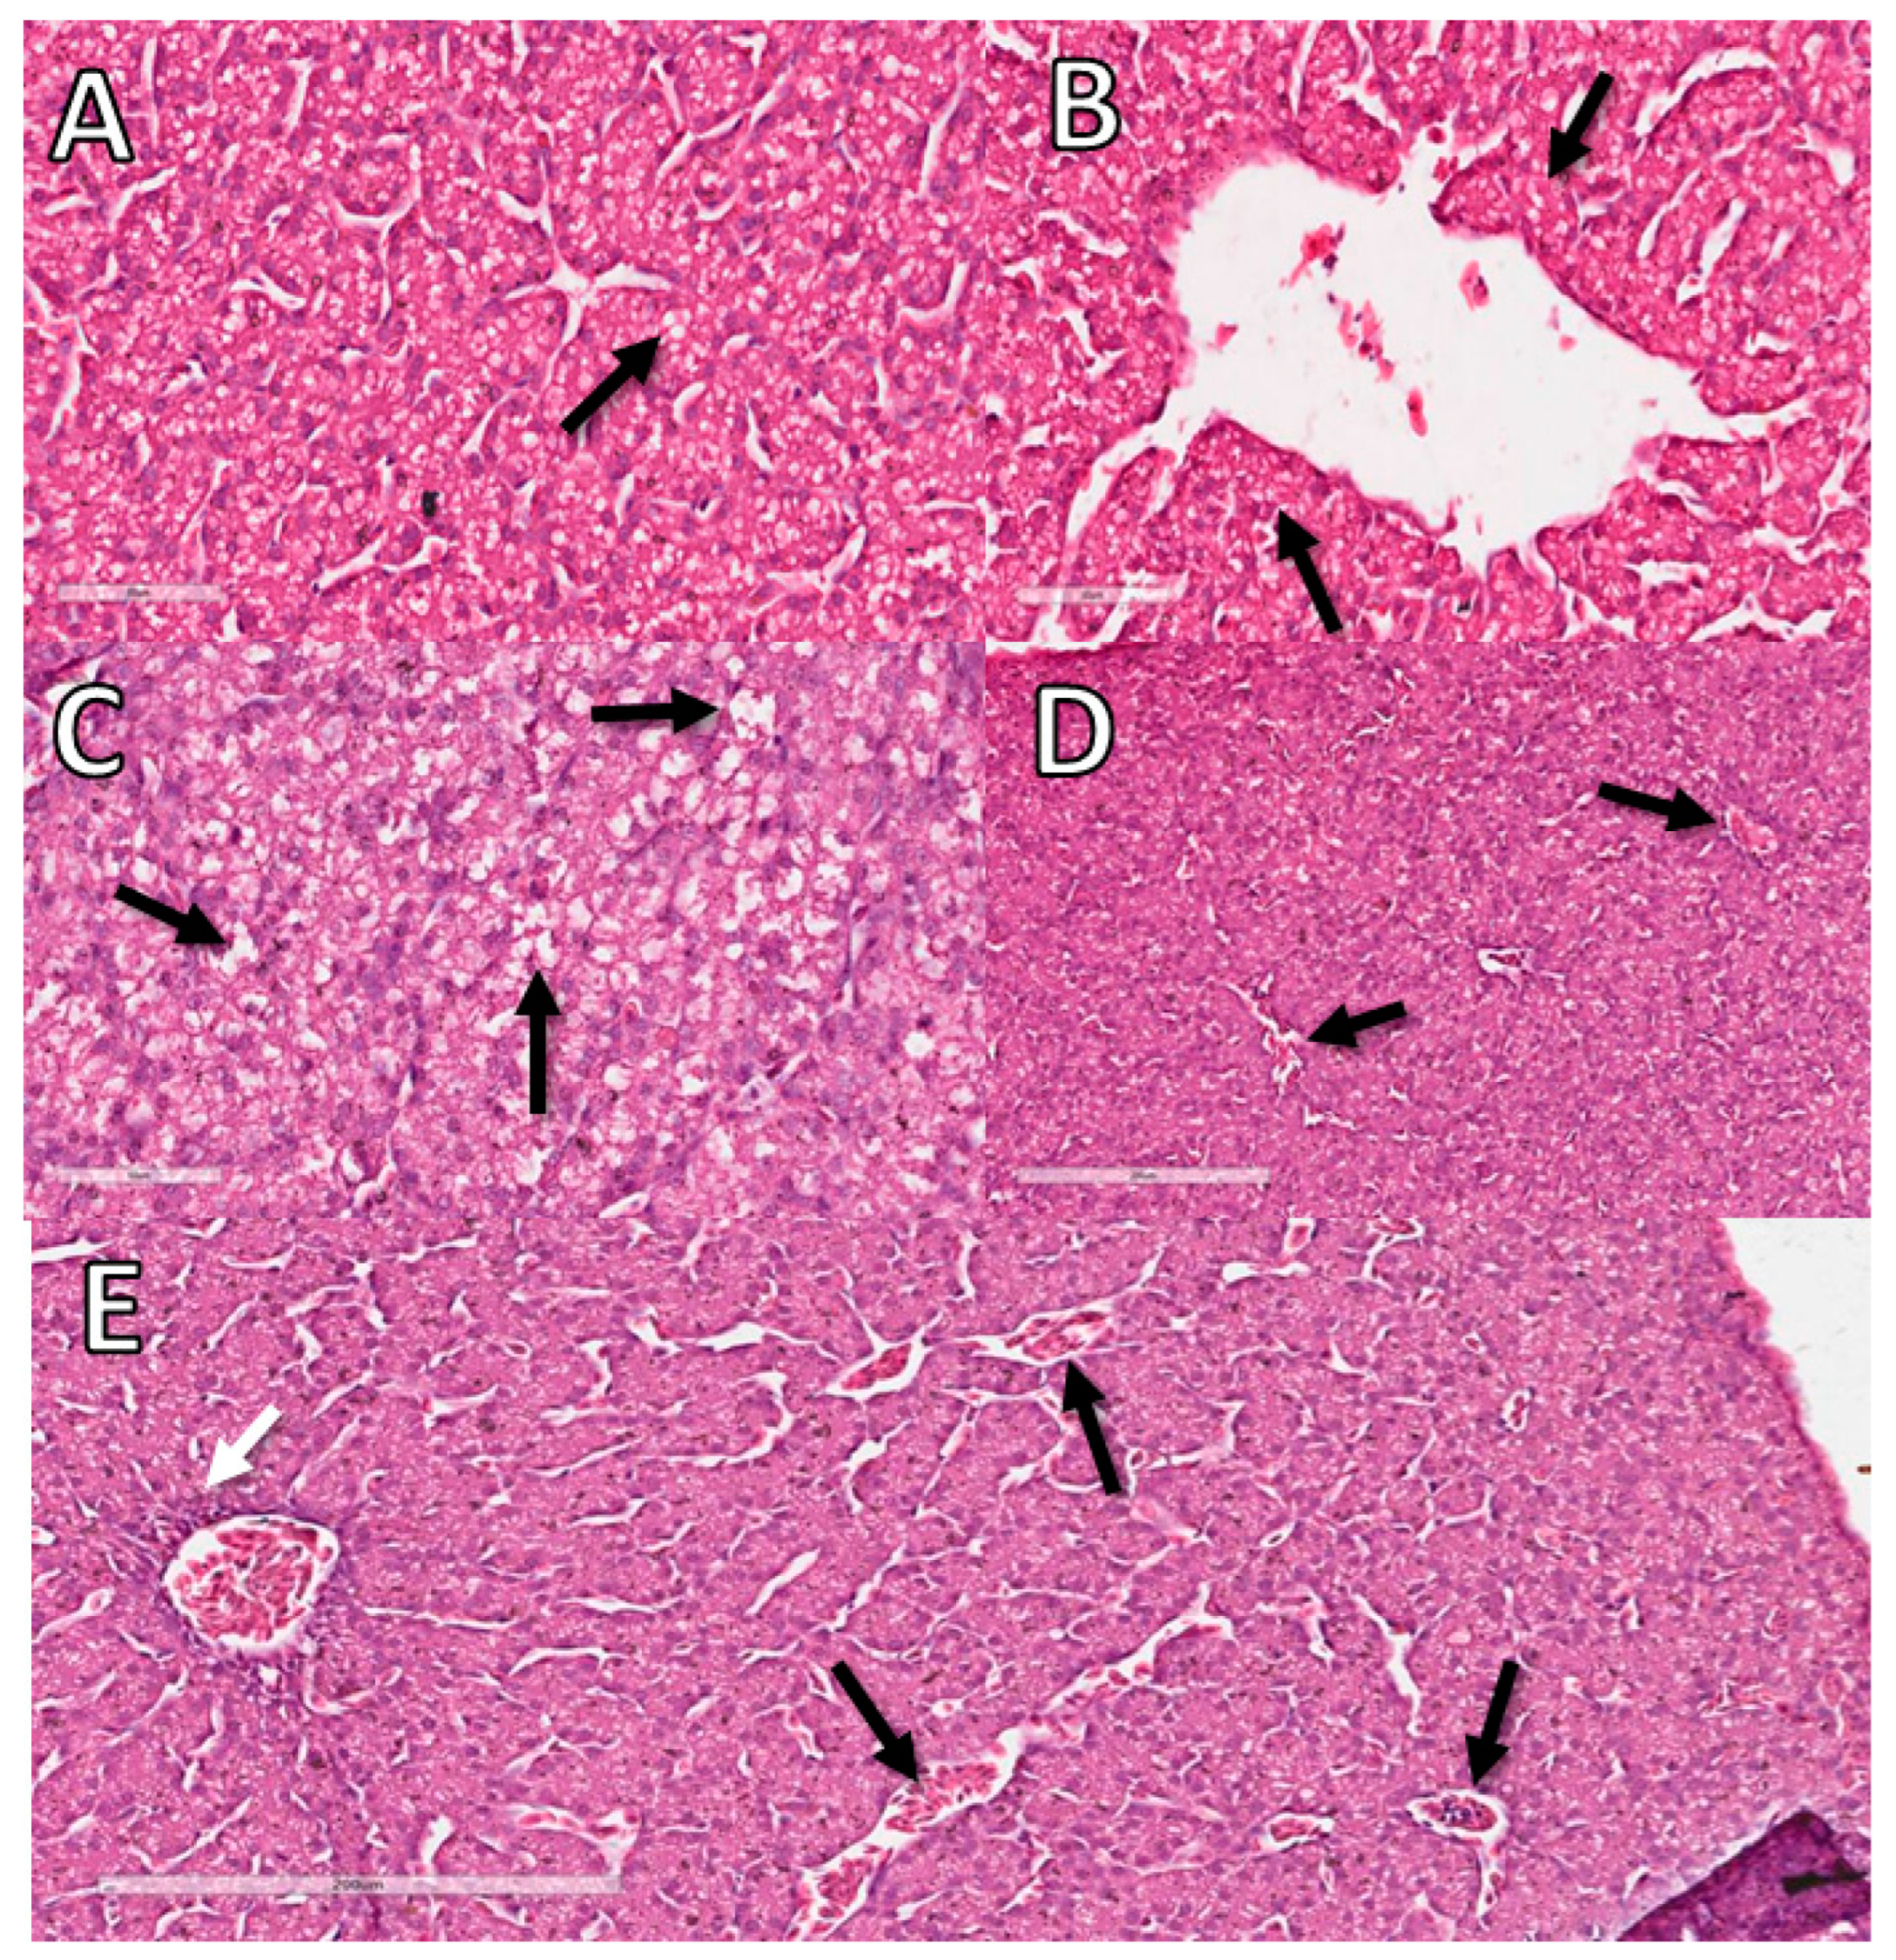

3.11. Liver Histopathological Analysis

| 10 EID | 12 EID | ||||||

|---|---|---|---|---|---|---|---|

| NC (CAM) | FG (CAM) | NC (SM) | DX (SM) | NC | FG | DX | |

| Inflammation | 0 (Mi: 0; Ma: 0) # | 1 (Mi: 0; Ma: 2) * | 0 (Mi: 0; Ma: 0) a | 0 (Mi: 0; Ma: 2) b | 0 (Mi: 0; Ma: 0) A | 0 (Mi: 0; Ma: 1) AB | 1 (Mi: 0; Ma: 2) B |

| Degeneration | 0 (Mi: 0; Ma: 0) # | 0 (Mi: 0; Ma: 0) # | 0 (Mi: 0; Ma: 0) a | 0 (Mi: 0; Ma: 3) a | 0 (Mi: 0; Ma: 0) A | 0 (Mi: 1; Ma: 1) AB | 1 (Mi: 1; Ma: 3) B |

| Necrosis | 0 (Mi: 0; Ma: 0) # | 0 (Mi: 0; Ma: 0) # | 0 (Mi: 0; Ma: 0) a | 0 (Mi: 0; Ma: 2) a | 0 (Mi: 0; Ma: 0) A | 0 (Mi: 0; Ma: 0) A | 0 (Mi: 0; Ma: 0) A |

| Circulatory change | 0 (Mi: 0; Ma: 0) # | 0 (Mi: 0; Ma: 1) # | 0 (Mi: 0; Ma: 0) a | 1 (Mi: 0; Ma: 3) b | 0 (Mi: 0; Ma: 0) A | 0 (Mi: 0; Ma: 1) A | 0 (Mi: 0; Ma: 0) A |